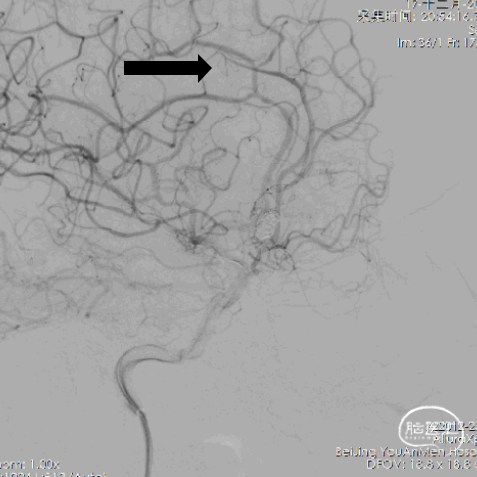

14、栓塞后造影。

栓塞后正位造影

术后给予替罗非班静脉泵入,术后第二天进行MRA。